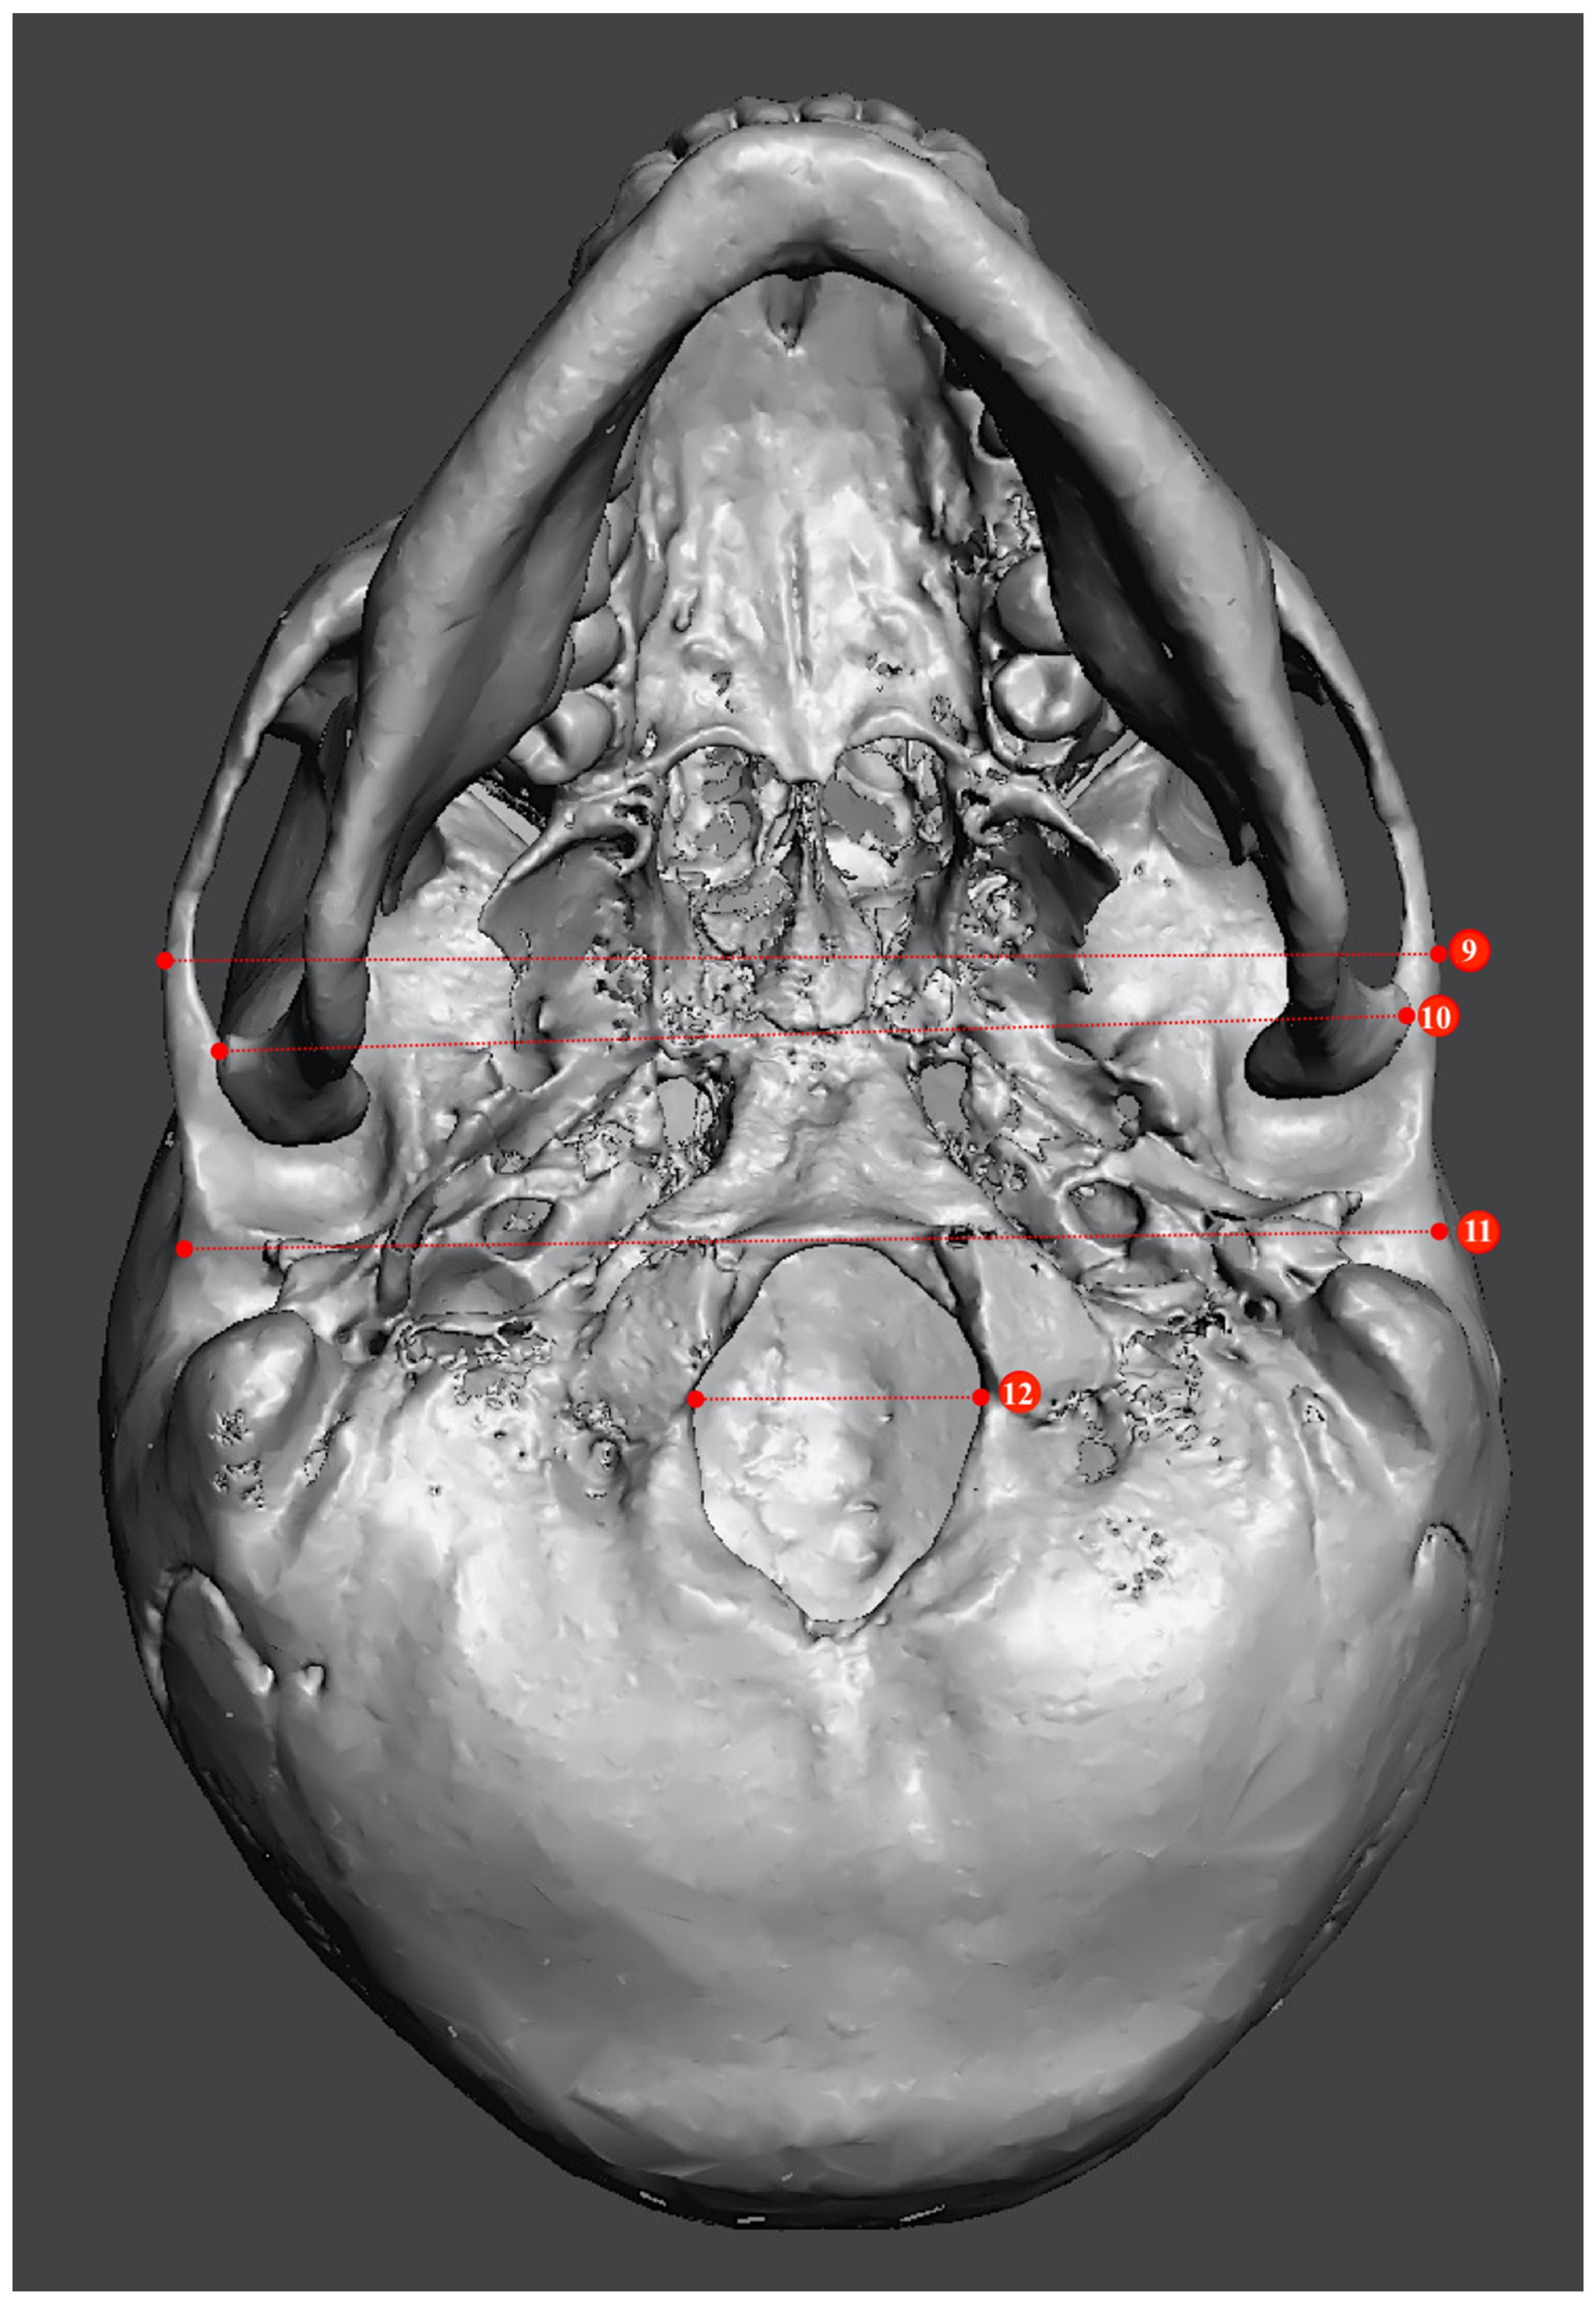

2.2. Study Sample Preparation and Data Collection

| Metric Measurements | |

|---|---|

| 1. Minimum frontal breadth (ft-ft) | 10. Bicondylar breadth (cdl-cdl) |

| 2. Orbital height | 11. Biauricular breadth (au-au) |

| 3. Upper facial height (n-pr) | 12. Foramen magnum breadth |

| 4. Parietal chord (b-l) | 13. Occipital chord (l-o) |

| 5. Glabella occipital length (g-op) | 14. Bigonial breadth (go-go) |

| 6. Mastoid length | 15. Basion–bregma height (ba-b) |

| 7. Mandibular length | 16. Basion–nasion length (ba-n) |

| 8. Maximum ramus height | 17. Frontal chord (n-b) |

| 9. Bizygomatic breadth (zy-zy) | 18. Nasal height (n-ns) |